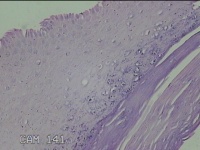

左侧手掌结节

性别

男

年龄

51岁

临床诊断

皮肤感染

一般病史

发现左手掌结节10余年。

标本名称

大体所见

灰白粉红色片状结节1.3x0.8x0.3cm一个,表面光滑,切面灰白粉红色,质软。